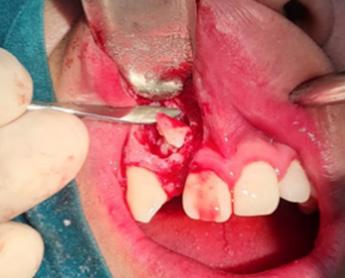

ABSTRACT

Systemic Lupus Erythematosus (SLE) is an autoimmune disease in which organs, tissues and cells are damaged by the exaggerated response of T cells and B cells, loss of immune tolerance against non-specific antigens of the organism. Lupus Enteritis (LE) is defined as vasculitis or inflammation of the small intestine that is diagnosed with the support of imaging and/or biopsy findings. Intestinal pneumatosis (PI) is a rare disease characterized by the presence of intramural gas in the gastrointestinal tract, associated with various clinical conditions, such as pulmonary diseases, gastrointestinal diseases and traumatic injuries, as well as autoimmune disorders.

A bibliographic search was carried out in databases such as PubMed, Nature, Elsevier and Google Scholar, with keywords such as “intestinal pneumatosis” and “lupus enteritis”.

Case presentation: Female patient with a history of surgery for intestinal obstruction, then returned due to a clinical picture of more or less 6 days, in poor general condition with hypotension 80/50 mmHg that did not improve with the administration of crystalloids, for which admission to the Intensive Care Unit (ICU) is indicated, with the need for vasopressors, interconsultation with surgery is carried out where it is decided to perform an exploratory laparoscopy, ruling out intestinal vascular compromise, after starting corticosteroids, the patient shows improvement and is discharged to the general ward in good condition and later home discharge.

Conclusion: Intestinal pneumatosis due to lupus enteritis is one of the rare manifestations with non-specific symptoms where prompt diagnosis and treatment is required. Giving a good response to corticosteroids and avoiding unnecessary surgical interventions.

Key words: Intestinal pneumatosis, lupus erythematosus, lupus enteritis,

INTRODUCCIÓN

El Lupus Eritematoso Sistémico (LES) es una enfermedad autoinmunitaria en la cual los órganos, tejidos y células se dañan por la respuesta exagerada de las células T y células B, perdida de la tolerancia inmune contra antígenos no específicos del organismo (1). La producción y eliminación defectuosa de anticuerpos, también depósitos de complejos autoinmunes, complemento y activación de citocinas (1), permiten el debut con las manifestaciones clínicas con la presencia de un 95 % de compromiso musculo esquelético, un 80 % cutáneas y con menos frecuencia las digestivas, 40 % (3), siendo así que la última que se menciona no forma parte del criterio diagnóstico

por la infrecuencia de los síntomas; la afectación gastrointestinal es una queja común que se observa en el 40 a 60 % de los pacientes con LES; se han descrito manifestaciones gastrointestinales clínicamente reconocidas en el 8 al 10% de los pacientes; por otro lado, los estudios de autopsia, informan hallazgos de compromiso gastrointestinal en el 60 a 70 % de los pacientes lo que sugiere un compromiso subclínico o no reconocido (11).

La Enteritis Lúpica (EL) es definida como una vasculitis o inflamación del intestino delgado con apoyo de hallazgos de imagen y/o biopsia; en la cual la tomografía es el examen de elección que nos muestra una mayor visibilidad de los vasos

RIIS UNIVALLE. Jul-Dic. 17(43), 2022; ISSN: 2075-6208 82

Pneumatosis intestinal por Enteritis lúpica, manifestación poco frecuente de lupus eritematoso sistémico Vargas-Machicado A. y Candia-Goitia J.

mesentéricos (signo del peine) (2), engrosamiento de los segmentos comprometidos (signo del tiro); el dolor abdominal es la forma de presentación más común que a veces viene acompañada por náuseas y diarrea. (4)

La Pneumatosis Intestinal (PI) es una enfermedad rara caracterizada por la presencia de gas intramural en el tracto gastrointestinal; se sabe que PI está asociado con varias condiciones clínicas, como enfermedades pulmonares, enfermedades gastrointestinales y lesiones traumáticas, así como trastornos autoinmunes (5). En particular, la PI se ve comúnmente en esclerosis sistémica (ES), pero rara vez en lupus eritematoso sistémico (5).

PRESENTACIÓN CASO CLÍNICO

Paciente femenino de 40 años con antecedentes de hipotiroidismo diagnosticado hace un mes, medicado con Levotiroxina 25 mcg, curso con infección por SARS CoV2 asintomática, lupus eritematoso sistémico diagnosticado hace una semana por la presencia de anticuerpos ANA (anticuerpos antinucleares) 1/80 (+), actualmente sin tratamiento. Fue hospitalizada hace dos semanas por un cuadro compatible con obstrucción intestinal alta, donde se realizó una laparotomía exploradora diagnostica, hallándose una pneumatosis intestinal con micro perforaciones, asas yeyunales ligeramente dilatadas, se realiza enterectomia de 20 cm por compromiso vascular con anastomosis término terminal, con un tiempo de internación de 9 días, se decide el alta hospitalaria en un buen estado general, estable, con buena tolerancia oral, buena cicatrización de herida y sin signos de inflamación.

La paciente acude 6 días después de su alta hospitalaria por nauseas acompañada de vómitos continuos con características biliosas además de astenia, adinamia, malestar general, palidez generalizada, dolor abdominal tipo cólico difuso sin alteraciones a nivel de conciencia espacio y persona pero somnolienta, Glasgow 13/15. Al examen físico a nivel de abdomen ruidos hidroaéreos hipoactivos con dolor a la palpación profunda en mesogastrio. Hemodinamicamente, se presenta con hipotensión (80/50 mmHg) que no mejora con la administración de cristaloides, por lo que requiere ingreso a terapia intensiva con necesidad de vasopresores (noradrenalina 0.09 a 0.016 mcg/kg/min) por 24 horas, además presenta signos compatibles con desnutrición severa por lo que se decide iniciar nutrición parenteral total sobre la base de una formula completa en bolsa tricameral; se coloca una sonda nasogástrica (SNG) que presenta alto debito en las primeras 24 horas con mejoría del cuadro clínico.

Laboratorio de ingreso: hemoglobina de 13gr/ dl (VN: 12.7-16.613gr/dl), leucocitos 5.900 mm3 (VN: 5.000-10.000 mm3), neutrófilos 75 % (VN: 42-75 %), plaquetas 560.000 mm3 (140.000420.000 mm3). Electrolitos: Na 133.4 mmol/L (VN: 135mmol/l-145mmol/l), K 3.22 mmol/L (VN: 3.5-4.5 mmol/L) presenta leve Hipokalemia, Cl 91 mmol/L (98-109 mmol/L). Con perfil hepático y pancreático donde los resultados fueron en parámetros normales. En el perfil inmunológico ANA 1/1860 (VN: <1/40), ENA (-) ANCA (-), hipocomplementemia a expensas de C3. La radiografía de tórax y abdomen: se describe en la figura 1.

RIIS UNIVALLE. Jul-Dic. 17(43), 2022; ISSN: 2075-6208 83

Vargas-Machicado A. y Candia-Goitia J.

Pneumatosis intestinal por Enteritis lúpica, manifestación poco frecuente de lupus eritematoso sistémico

Figura 1a: Radiografía de tórax AP,rebela sobreelevación del diafragma izquierdo por distención de asas intestinales en pila de moneda, asociado a presencia de aire en su inferior.

Figura 1b: Radiografía abdomino pélvica AP con imagen sugerente de presencia de aire en asas intestinales, probable relación con neumatosis intestinal.

TAC de abdomen con contraste: reporta pneumatosis en yeyuno distal y en íleon que se asocia con burbujas de neumoperitoneo con presencia de signo de rigler, atelectasia en lóbulo inferior y liquido libre intraabdominal con asa adyacente Figura 2

Por todo lo encontrado y los antecedentes, se realiza nueva interconsulta con cirugía general, se decide someterla a una laparoscopia exploratoria para descartar compromiso vascular intestinal y evaluar vitalidad de asas, los hallazgos fueron: Yeyuno e íleon distal rosado con peristaltismo presente, a

nivel de yeyuno proximal presencia de pneumatosis intestinal en todo el borde mesentérico; se evidencia marco colónico en buenas condiciones y sin datos de isquemia (Figura 3). No se llegó a realizar estudio histopatológico.

RIIS UNIVALLE. Jul-Dic. 17(43), 2022; ISSN: 2075-6208 84

Figura 2. TAC Abdominal con contraste corte transversal

J.

Vargas-Machicado

A.

y Candia-Goitia

Después de la laparoscopia exploratoria y ante la posibilidad de una neumatosis intestinal por enteritis lúpica , en coordinación con el servicio de reumatología, se decide la administración de altas dosis de metilprednisolona (1gr vía EV por 3 días) y se solicitan nuevos estudios AC anti- B2 glicoproteína IgM 0.4 U/ml, IgG 3.3 U/ml (VN: IgM - IgG <5 U/ml), Anticoagulante lúpico (-) y anti-cardiolipina IgM 0.4 mpl-au/ml, IgG 3.4 glp-U/ ml (VN para resultado positivo: IgM >7 MPL-U/ml – IgG > 10 GLP-U/ml).

Citoquímico de líquido peritoneal: ligeramente opalescente, trazas de sangre, proteína +, glucosa 141 mg/dl, proteínas totales 2,7 g/dl, LDH: 249 U/L.

Después de 2 días en la Unidad de Terapia Intensiva se descontinua vasopresores, no se evidencian datos de obstrucción intestinal alta, canalizo gases, tolero líquidos vía oral; posteriormente la paciente es dada de alta a sala general, donde completa los pulsos de metilprednisolona y continua el aporte nutricional por vía oral con buena tolerancia, además de catarsis semilíquida, después de 48 horas solicita su alta voluntaria a otra institución por lo que se limita a conocer la evolución actual.

DISCUSIÓN

En la PI asociada a las enfermedades autoinmunes (LES, Síndrome antifosfolipico, Dermatomiositis, Esclerodermia), se describió que, de 15 casos asociada a LES, en la mitad de los pacientes se comprobó la aparición de vasculitis (6). Los corticoesteroides (CS), que a menudo se

administran a pacientes con enfermedades autoinmunes, tienen un mecanismo de acción, disminuyendo el tejido linfático en las células de Peyer del intestino y resultando en la degeneración de la mucosa que conduce a la entrada de gas en el peritoneo y la pared intestinal. (6). La enteritis lúpica, aunque infrecuente, en cuanto al rango de incidencia que abarca lo que es un 0.2 % a 9.7 %, y un rango indefinido, en lo que refiere la relación de EL y LES, sigue siendo una complicación rara de LES, que puede asociarse con vasculitis en otros órganos y generalmente indicando una enfermedad activa lo que justifica un diagnóstico rápido e inmunosupresión agresiva (7) (8). Un mecanismo propuesto para la enteritis lúpica es la activación del complemento; la activación de este podría promover una lesión microvascular difusa y el aumento de la permeabilidad vascular (12).

La PI no es muy común en la práctica médica, aún más en relación a una enteritis lúpica por LES ya que ambos tienen un espectro de síntomas muy inespecíficos o asintomático; en pacientes con LES que refieran dolor abdominal acompañado de nauseas, diarreas y vómitos se debe sospechar posibles casos de enteritis lúpica y acudir con imágenes ante la sospecha de pneumatosis intestinal; dentro de la evaluación inicial, se realizará una anamnesis completa, destacando las características del dolor, localización, cronología, desencadenantes, náuseas, vómitos o alteraciones del ritmo intestinal, características de la deposición y signos de sangrado, respuesta a la analgesia, tratamientos que puedan enmascarar síntomas y datos de actividad del lupus como lesiones cutáneas, aftas o síntomas

RIIS UNIVALLE. Jul-Dic. 17(43), 2022; ISSN: 2075-6208 85

Figura 3. Hallazgos de laparoscopia exploratoria

y Candia-Goitia J.

generales como pérdida de peso o síntomas B. Es fundamental realizar un diagnóstico diferencial con cuadros infecciosos, como también la terapia inmunosupresora, para así llegar a un diagnóstico correcto y oportuno, así mismo valorando la necesidad de un tratamiento quirúrgico (8). Por la parte de laboratorio se debe incluir hemograma, hemostasia, bioquímica general, reactantes de fase aguda, junto con la determinación de anticuerpos anticardiolipina, anticoagulante lúpico y niveles de complemento. El estudio de imagen debe ser fundamental como ser la ecografía, TAC abdominal y radiografía de abdomen (8) (9).

Nuestra paciente presento un cuadro clínico inespecífico, con dolor abdominal, con disminución de los ruidos hidroaéreos, náuseas, vómitos biliosos, laboratorios en rangos normales, pero si ANA (+) e hipocomplementemia a expensas de C3, dándonos un posible diagnóstico de enteritis lúpica. La TAC de abdomen, reveló signos específicos de neumatosis intestinal, como ser la presencia del signo de rigler (signo de la doble pared), pero sin datos específicos de enteritis lúpica, por medio de imagen, como ser la dilatación de la pared o signo diana y el signo de peine.

En cuanto al manejo, no hay un consenso establecido sobre la mejor elección terapéutica, debido a la falta de ensayos clínicos sobre el tema. El tratamiento habitual e inicial es el uso de corticoides en pulsos endovenoso, con un descarte previo de alguna alteración en tubo digestivo, por eso se debe realizar una laparoscopia exploratoria, descartando microperforaciones, necrosis, para luego proceder con el inicio de pulsos de metilprednisolona por tres días, como en el caso de nuestra paciente (10).

CONCLUSIÓN

La pneumatosis intestinal por enteritis lúpica se debe considerar como posible manifestación inicial o complicación en pacientes con LES, implicando un diagnóstico dificultoso ya que al tratarse de una sintomatología digestiva, que en la mayoría de los casos es inespecífica, Así también, es importante realizar un diagnóstico diferencial con un buen criterio clínico, realizar una buena historia clínica sin escatimar detalles, también contar con un protocolo diagnóstico y manteniendo un seguimiento constante para brindar un diagnóstico y manejo adecuado, sobre todo para evitar intervenciones quirúrgica agresivas e innecesarias.

RIIS UNIVALLE. Jul-Dic. 17(43), 2022; ISSN: 2075-6208 86

Pneumatosis intestinal por Enteritis lúpica, manifestación poco frecuente de lupus eritematoso sistémico Vargas-Machicado

REFERENCIAS BIBLIOGRÁFICAS

1. Kiriakidou M, Ching CL. Systemic lupus erythematosus. Ann Intern Med [Internet] 2020; 172(11): ITC81-96. Disponible en: http://dx.doi.org/10.7326/aitc202006020

2. Brewer BN, Kamen DL. Gastrointestinal and hepatic desease in sistemic lupus erythematosus. Rheum Dis Clin North Am [Internet]. 2018; 44(1): 165-75. Disponible en: http:///dx.doi. org/10.1016/j.rcd.2017.09.011

3. Jameson; Fauci; Kasper Longo. Principios de medicina interna (2T).19ª ed. Nueva York, NY, Estados Unidos de América; Mc Graw-Hill education Publishing; 2018

4. Barrera O M, Barrera M R, de la Rivera M V, Vela U J, Mönckeberg F G. Lupus enteritis as initial manifestation of systemic lupus erythematosus. Report of one case. Rev Med Chil [Internet]. 2017;145(10):1349–52. Disponible en: http://dx.doi.org/10.4067/S0034-98872017001001349